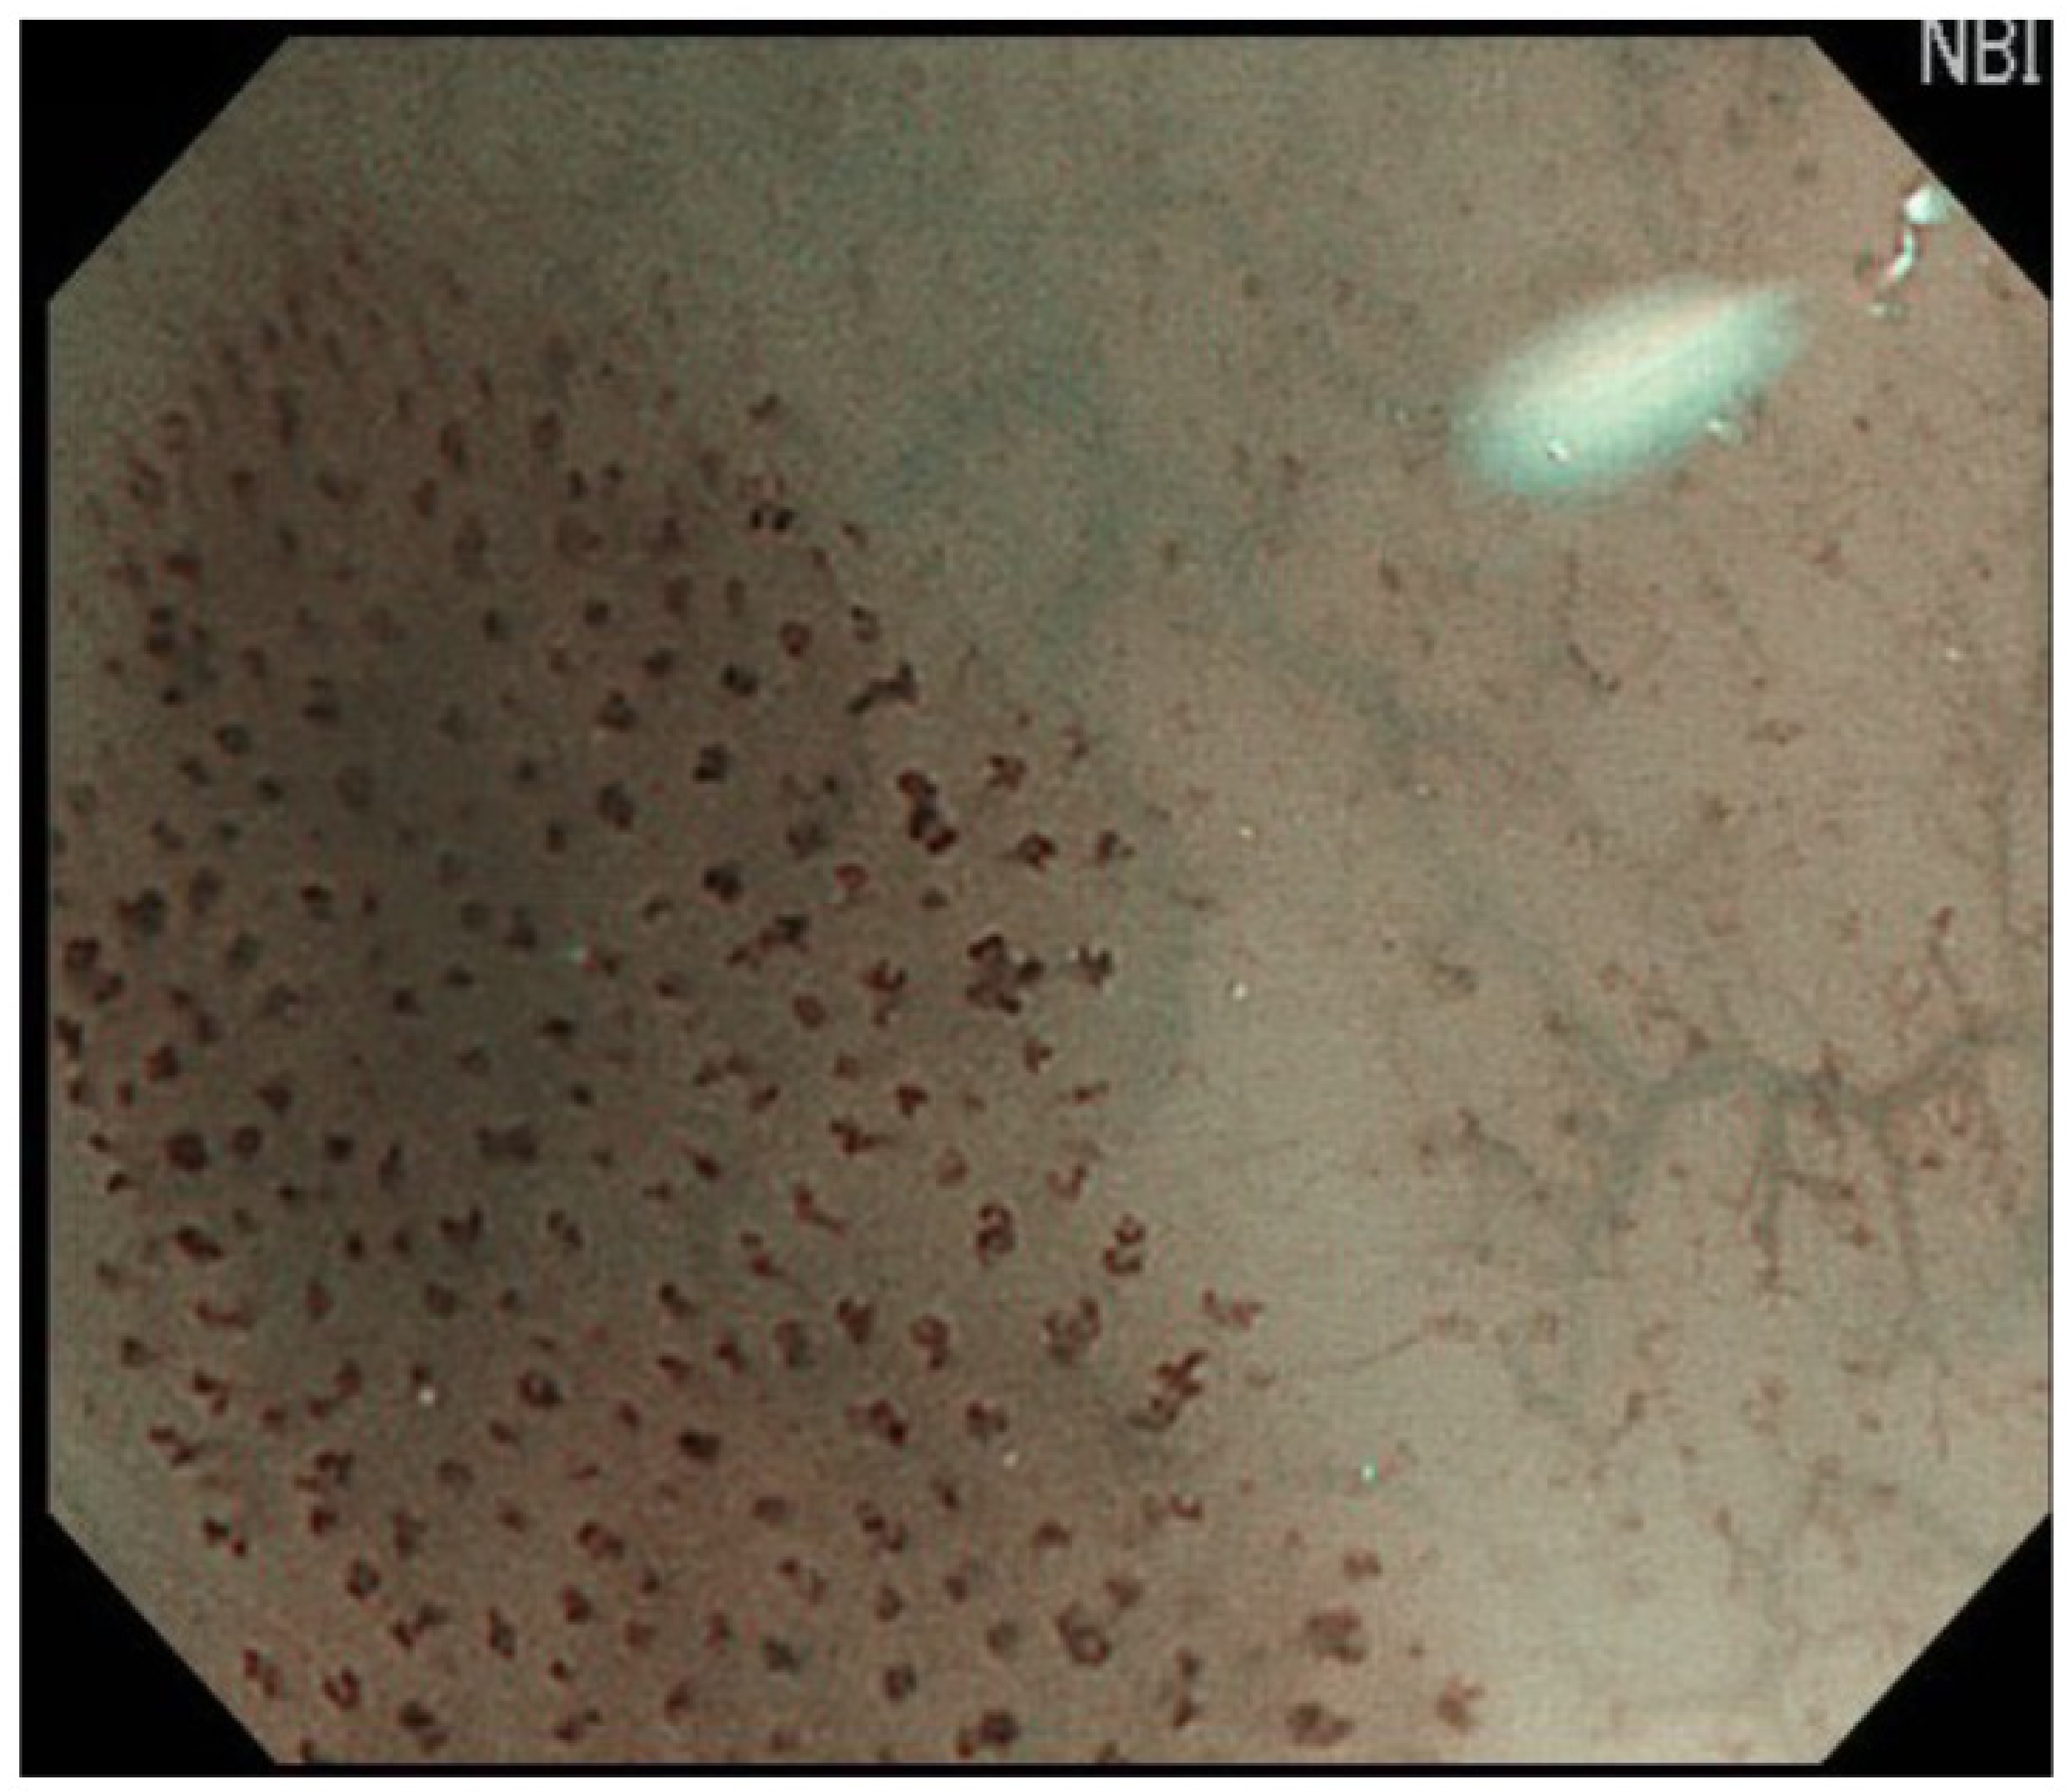

2.2. Endoscopic Diagnosis of SCC

3.2. Diagnosis of Cancer Invasion Depth by White-Light Endoscopy and Magnifying Endoscopy